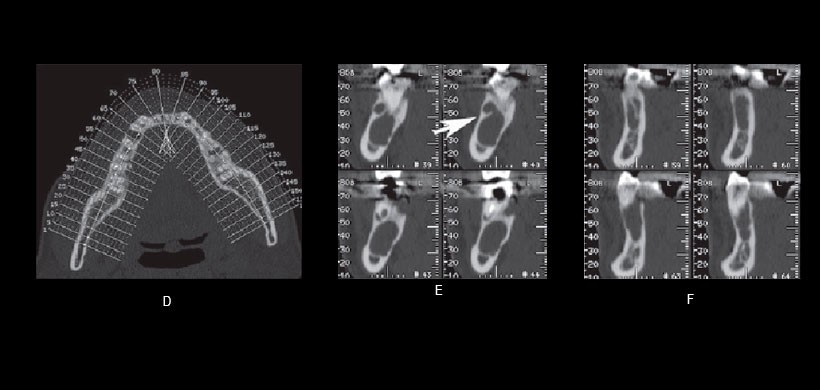

Fig 3. Imágenes de tomografía computarizada de la mandíbula del paciente. (D) Imagen de referencia de la reconstrucción ortogonal. Los números asignados son equivalentes al número de imagen de cada vista ortogonal. (E) Las vistas ortogonales que representan el tumor odontogénico queratoquístico revelaron el tabique dentro del KCOT (flechas). (F) Vistas ortogonales que identifican el ameloblastoma.